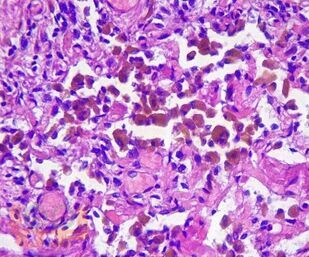

Учебное пособие разработано по дисциплине «Патологическая анатомия - патологическая анатомия головы и шеи» в соответствии с Федеральным государственным образовательным стандартом высшего профессионального образования для студентов, обучающихся по основным образовательным программам высшего образования - программам специалитета по специальности «Стоматология».

В учебном пособии представлен теоретический материал, перечень макропрепаратов и микропрепаратов, демонстрирующих типовые проявления патологических процессов. В цветных иллюстрациях и в описании микропрепаратов сделан акцент на наиболее важных гистологических изменениях, позволяющих на светооптическом уровне диагностировать и дифференцировать состояния, отклоняющиеся от нормы, в том числе с использованием различных гистологических окрасок. Пособие помогает выделить главные аспекты изучаемых патологических процессов, организовать и конкретизировать учебный процесс.